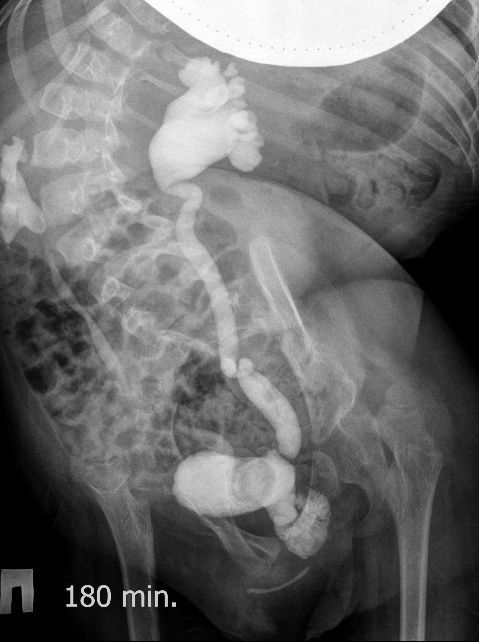

Для того, чтобы продемонстрировать степень ортопедических проблем и облегчить задание (или усложнить :) ) добавляю обзорную рентгенограмму брюшной полости

Поскольку откликов нет, добавляю экскреторные урограммы этого же пациента

Нейрогенный мочевой пузырь (?), МКБ, конкремент мочевого пузыря, двухсторонний мегауретер, конкремент правой почки.

И что законтрастировалось на экскреторных урограммах около мочевого пузыря?

Если честно, и я изначально не совсем понял, где находится конкремент (а это конечно же конкремент), локализованный на урограммах. При первичном исследовании на УЗИ его я не видел (либо он спрятался за тенью конкремента мочевого пузыря, либо я обрадовался редкой находке конкремента такого размера в мочевом пузыре - 2.5 см, и не посмотрел что ниже). Тем не менее при ретроспективном анализе архивированных сонограмм, как мне кажется, он попал в один из сканов, м.б. не совсем чётко.

И всё -же, где конкремент :?:

Возможно, в дивертикуле либо в нижней трети мочеточника..

Верификация:

Выдержка из протокола операции- "...вскрыт мочевой пузырь, обнаружен камень 4 х 3х 2.5 см, плотный, удалён. При дальнейшей ревизии мочевого пузыря обнаружен вколоченный камень в шейке мочевого пузыря и в уретре, удалён камень 2 х 1.5 х 1.5 см. При осмотре устья левого мочеточника - последний зияет, мочеточник расширен до 1 см, учитывая расширение мочеточника, проведена антирефлюксная пластика по Грегуару..."